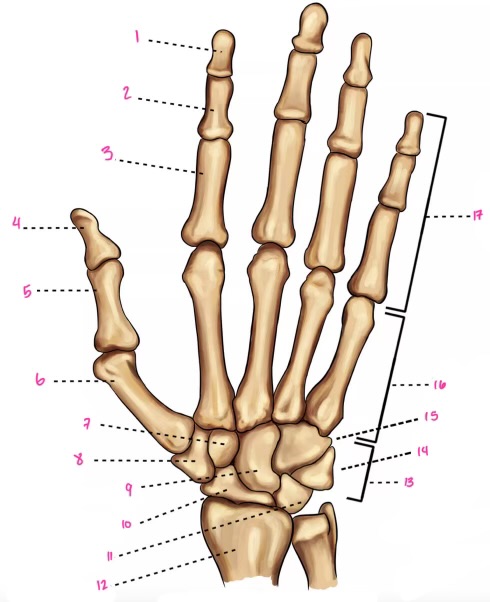

1

1

2

2

3

3

4

9

5

10

6

11

7

14

8

15

9

16

10

17

11

18

12

1

13

2

14

3

15

4

16

5

17

6

18

7

19

8

20

9

7

22

8

23

9

24

10

25

11

26

13

27

14

28

15

29

16

30

17

Phalanxes